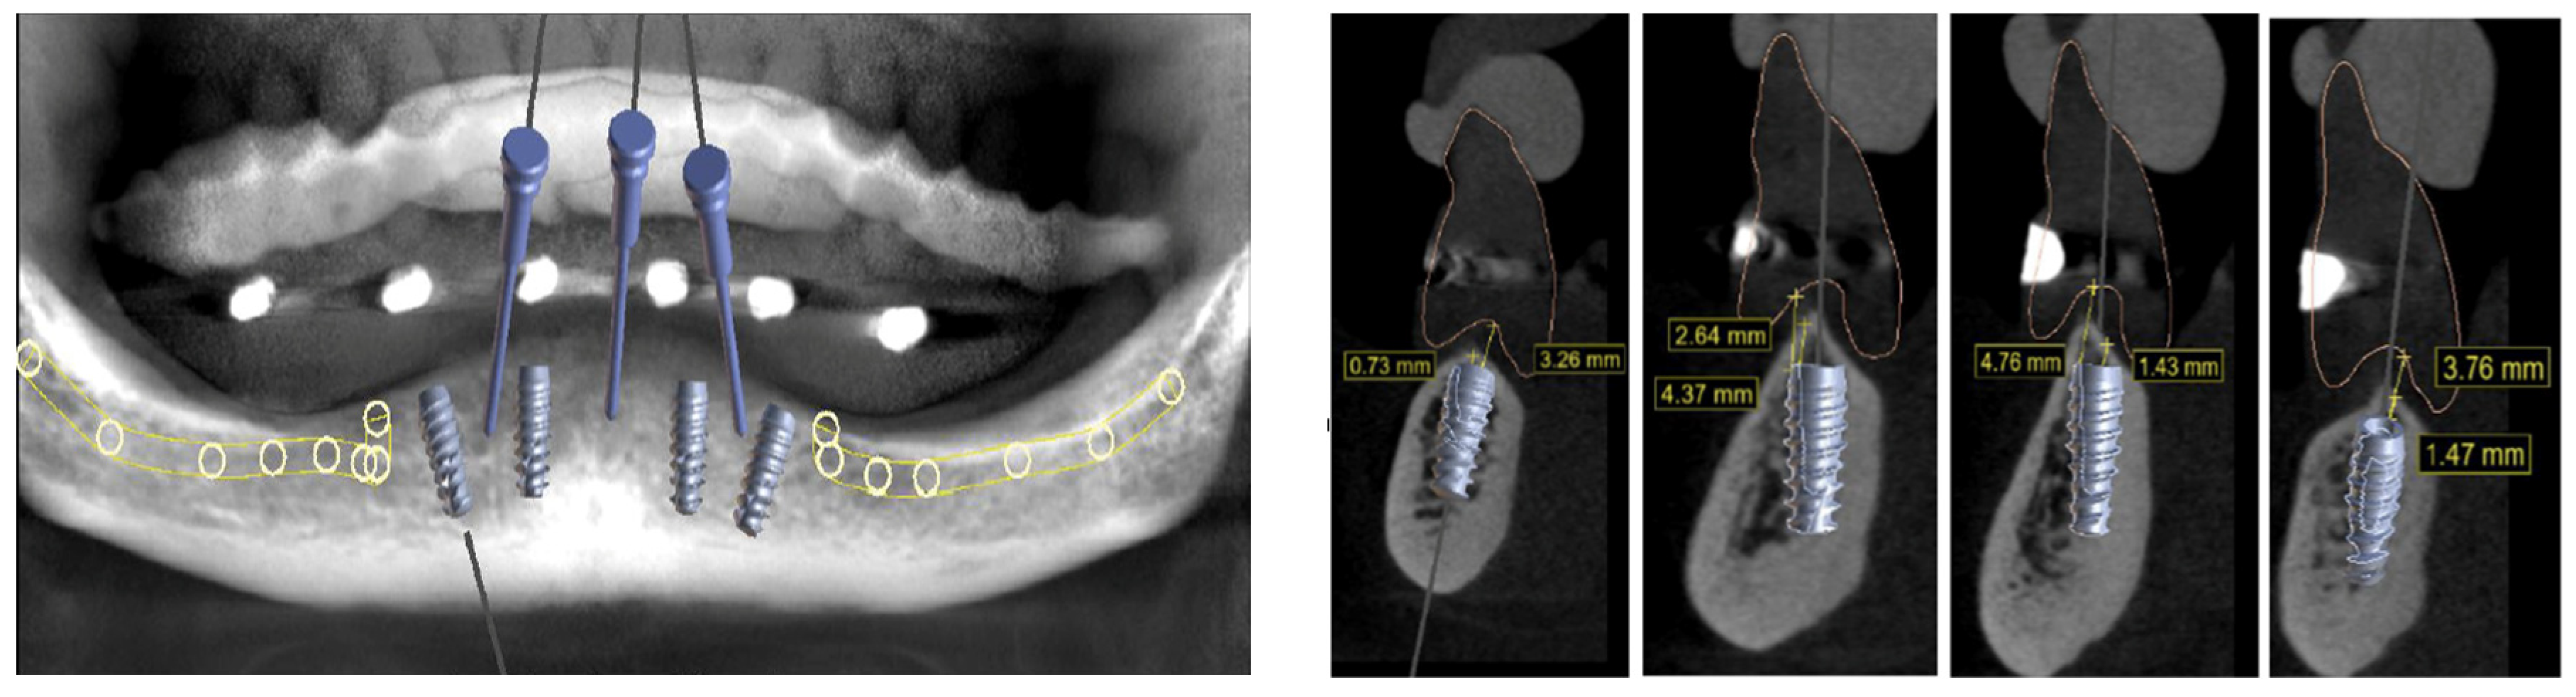

2. Case Report